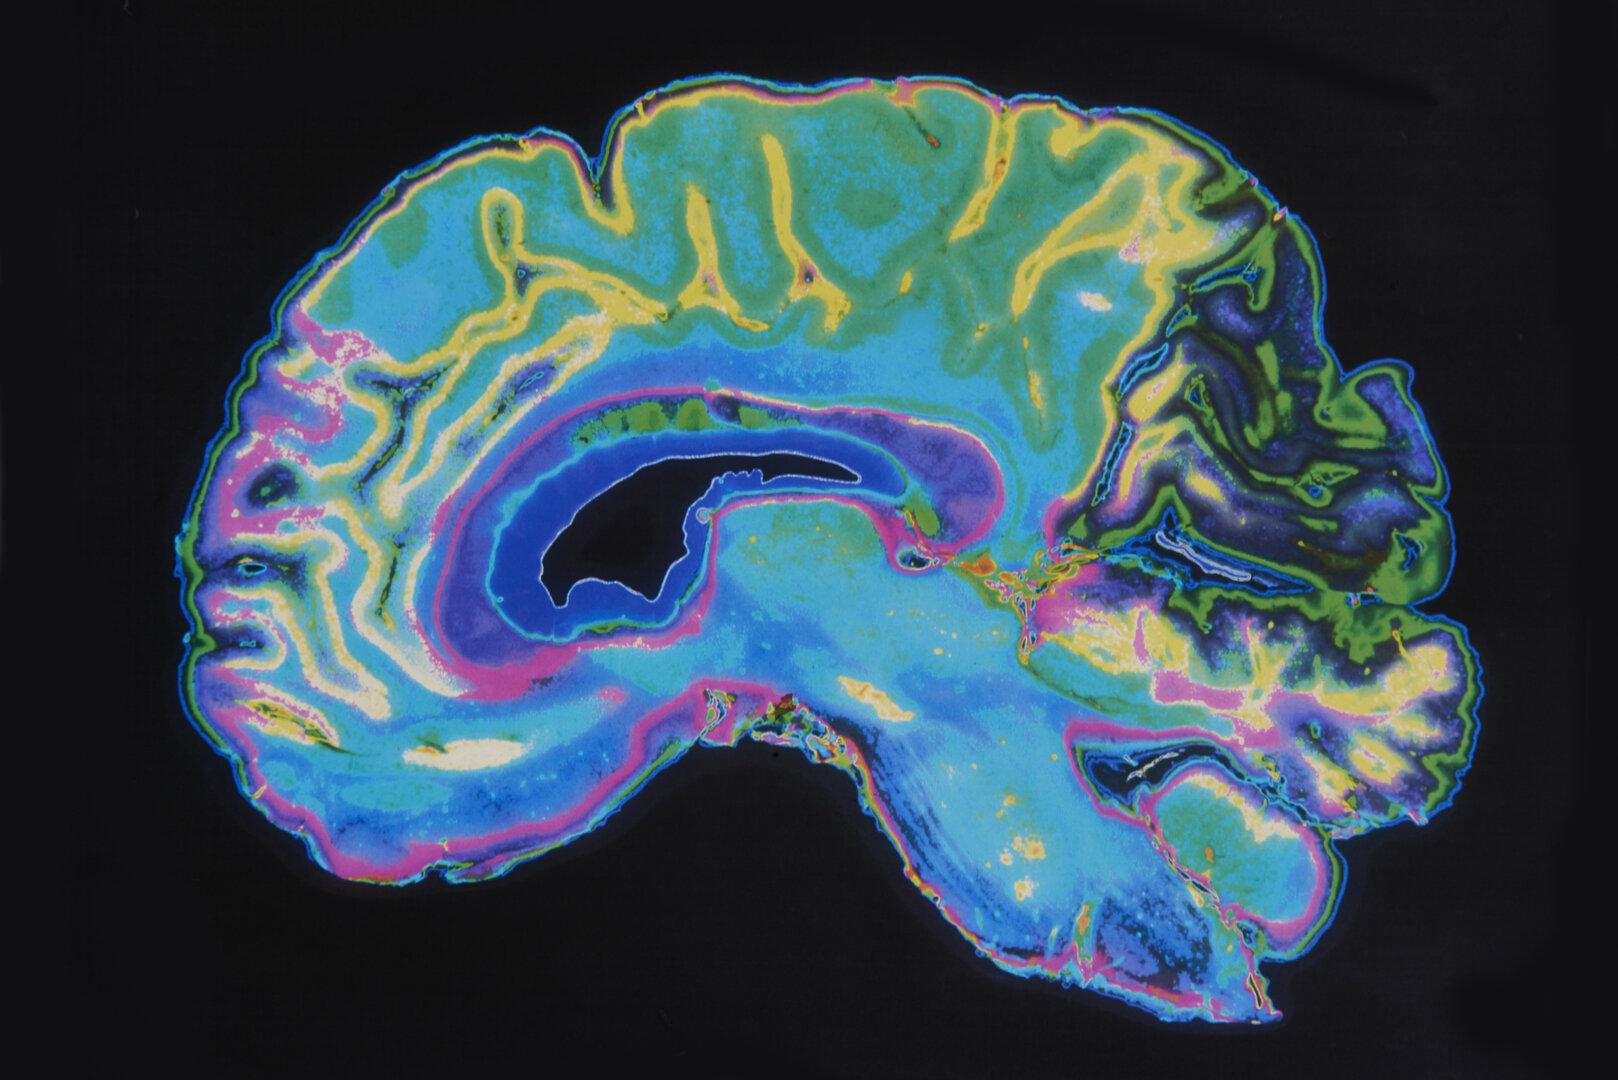

Studie: 7 Aktivitäten, die Ihr Gehirn vor Demenz schützen

Positive Effekte waren schon im mittleren Lebensalter feststellbar, nicht erst, wenn Demenzsymptome auftraten.